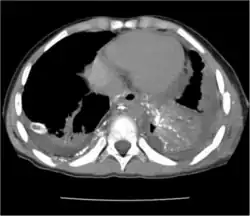

Chest X-rays can detect a chylothorax. It appears as a dense, homogeneous area that obscures the costophrenic and cardiophrenic angles. Ultrasounds can also detect a chylothorax, which appears as an echoic region that is isodense with no septation or loculation. However, neither a normal chest x-ray nor an ultrasound can differentiate a chylothorax from any other type of pleural effusion.[1]

The cisterna chyli can be found in a thoracic MRI, making it possible to confirm chylothorax. However, MRI is not the ideal method to scan the thorax, and so it is rarely used. Another diagnostic technique is conventional lymphangiography. It is rarely used since there are equally sensitive yet less invasive techniques available to identify a chylothorax. Lymphangiography procedures use the contrast dye agent lipiodol, which is injected into the lymphatic vessels. The chylothorax shows up on the images and identifies the source any leak in the thoracic duct.[1]